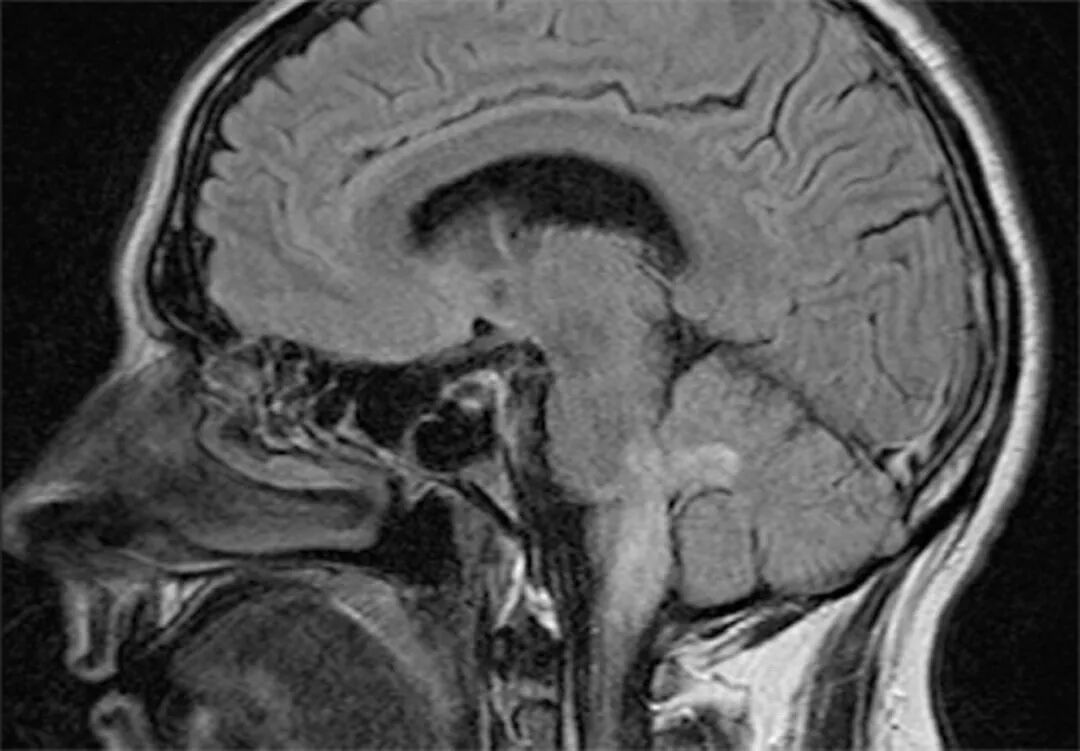

李斯特菌感染最常见的中枢神经系统表现是脑膜脑炎。脑炎很少情况下会进展为脑脓肿,菱脑炎(脑干脑炎)较少见。李斯特菌脑膜脑炎的临床表现从轻度疾病(发热和精神状态改变)到暴发性病程(昏迷)不等。大多数成人呈亚急性疾病。

脑干脑炎是李斯特菌的特征表现

脑神经麻痹、脑脊液淋巴细胞增多、脑脊液蛋白水平升高和葡萄糖水平降低等亚急性表现,可能与结核性或真菌性脑膜炎相似。这类患者的脑脊液李斯特菌培养常为阳性。

临床应监测治疗反应(体温、临床体征和症状)。对于经过数日治疗仍持续发热或仍有其他体征或症状提示疗效较差的患者,应复查血培养;对于有中枢神经系统感染患者,还应复查脑脊液培养,如果初始MRI检查结果异常,还要复查MRI。